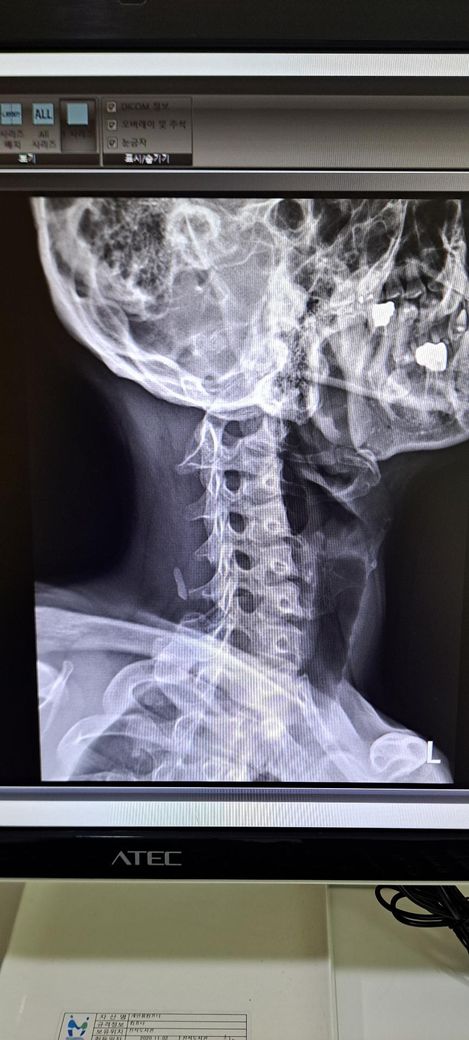

x ray 촬영한 영상인데 골반 틀어짐 및 전방경사 심각한가요? 골반 틀어짐은 어느 쪽을 교정해야 하며 골반 틀어짐 및 전방경사 교정 방법을 알려주시면 감사하겠습니다 .

또한 일자목도 있다는데 심각한 정도인가요?

목은 일자목 경향은 있으나 심한 변형보다는 자세성 문제로 보이며 교정운동이 중요합니다.

또한 목은 일자목이 있으며 역C자 수준 까지는 아니라고 생각됩니다.

정면 사진상 골반의 좌우높이 차이가 관찰되며, 이는 대퇴골의 위치변화와 연관되어 보입니다. 측면 사진에서 요추의 곡선이 다소 꺾여 있는 양상이 보여 골반 전방경사 가능성이 큽니다. 정면 영상에서 척추가 일직선이 아니라 완만한 S자 형태로 휘어있는 측만 소견이 보입니다. 심각한 수준은 아니나 지속적인 관리가 필요한 상태입니다. 측면 사진상 경추의 커브를 보면 일자목 상태입니다. 골반이 높은쪽의 근육은 이완시키고, 낮은쪽과 약해진 둔근, 복근을 강화하는 운동이 필요합니다. 전방경사 완화를 위해 장요근 스트레칭과 프랭크 같은 코어 운동이 효과적입니다. 흉쇄유돌근 스트레칭과 더불어 등 근육을 강화하여 어깨를 펴는것이 급선무입니다.

보여주신 X-ray를 보면 우선 첫번째 사진에서 경추전만이 무너져서 일자목을 넘어 역 C자가 만들어진걸 볼 수 있습니다. 평소 고개를 앞으로 굽히지 않는 경추전만 자세 교정이 필요하겠으며 아래 영상 보시면서 자세를 교정해보시기 바랍니다. 아래 영상은 디스크에 대한 영상이지만 결국 교정해야할 자세는 같습니다.

x-ray 결과로 보아서는 경추C자 곡선이 반대로 되어 있어 일자목이 심해 보이며 골반 틀어짐과 척추측만증이 있는 것으로 보입니다.